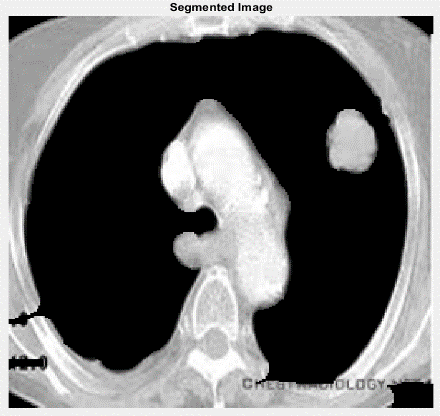

Region wrapping is the step of operations which eradicate incorrect boundaries and bogus regions by merging adjacent regions based on the gray value of these regions. Region wrapping is accomplished to group the tumor regions detected together as single layer of region after the thresholding. The complete segmentation results of each stage are illustrated in Figure 2.

(a) Original lungs image

(b) SLIC -Cancer segmented

(c) Optimal Thresholding (Enhanced image)

(d) Region Wrapping-abnormal malignant

Figure 2. Segmentation Results: a) Original Image; b) SLIC; c) Optimal Thresholding; d) Region Wrapping

In Figure 6, we shown the result of preprocessing stage, in which we used gamma correction-based image enhancement to improve the contrast of original image and that also clearly depicted in the above Figure 6. Next implementation is that segmentation of brainy region means removal of skull content available in the whole image as shown in Figure 7.

Once the gray segmentation output is obtained, we are performing pseudo color transformation using labelling method in morphological operations. This transformation will retain the highly infected regions if any in the segmented lungs cancer area. The output of segmented and pseudo color converted is illustrated in Figure 6.

Figure 6. Segmented image and pseudo color transformed image

Figure 6 shows the final result of lungs cancer detected content the classification results from our proposed method of ICCAN. Figure 7 is shown for the pictorial representation of performance comparison of our proposed with the existing algorithms of researches [28-31]. Table 1 is for numerical comparison.

Figure 6, shows the final result of tumor detected content the classification results from our proposed method of ICCAN.